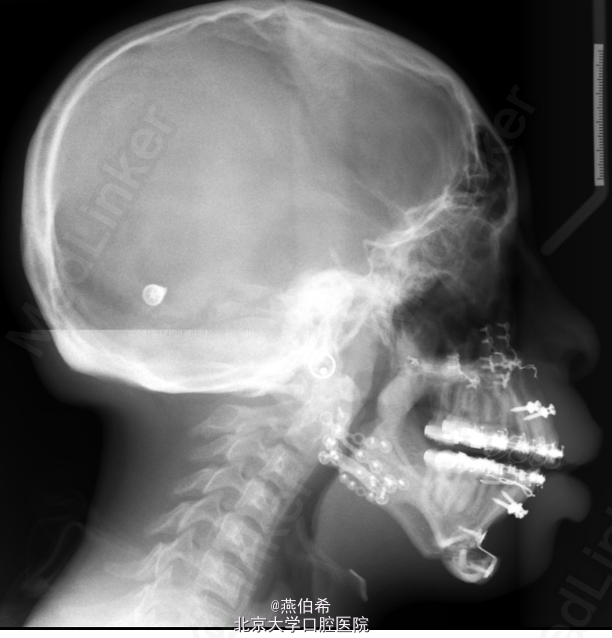

11岁非洲裔男孩,主诉牙不齐。 在New York-Presbyterian Morgan Stanley Children's Hospital (US news 儿科专业全美第9)接受颅面治疗,确诊为Treacher Collins综合征 婴儿时曾行气道造口,后右耳曾行鼓膜造口和置管以及左耳成型术

突面型,嘴唇无法闭合,口内10mm前牙开牙合,右侧3类磨牙关系,左侧1类磨牙关系。 头侧片显示极高角

Treacher Collins综合征 扩弓解决宽度不调,拔4个4矫正牙量骨量不调, 后行口外反L行截骨术矫正颌骨问题